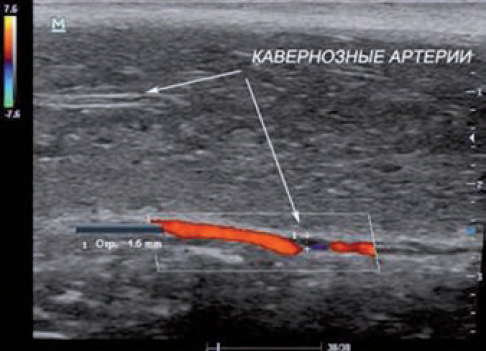

- ультразвуковое исследование (УЗИ) с использованием доплерографии сосудов полового члена (рис. 1, 2);

Рис. 1. Ультразвуковая доплерография сосудов полового члена в норме: а — 1, 2 (между стрелками) — половой член вне эрекции; 3 — кавернозные тела нормальной эхогенности; 4 (стрелки) — мочеиспускательный канал; 5 — мошонка; б — 1, 2 — половой член во время эрекции; 3 — кавернозные тела во время эрекции; 4 (стрелки) — мочеиспускательный канал; 5 — мошонка

Рис. 2. Ультразвуковая доплерография сосудов полового члена. Выделены кавернозные артерии

Использовать доплерографию полового члена для диагностики ЭД начали с конца 70-х — начала 80-х гг., а в конце 90-х гг. XX в. в связи с появлением и распространением ингибиторов ФДЭ-5 она стала широко распространенным методом исследования [14]. Согласительный Комитет по изучению эректильной дисфункции в июне 1999 г. рекомендовал УЗИ полового члена с интракавернозным фармакотестом как первый специализированный метод обследования пациентов с ЭД. Было отмечено, что данное исследование характеризуется малой инвазивностью, высокой информативностью и относительно невысокой себестоимостью [15]. Современное комплексное УЗИ полового члена включает в себя следующие технологии: B-режим, доплеровские методы, состоящие из импульсно-волнового режима, так называемого PulseWave, цветового энергетического доплеровского картирования (Collor Doppler Energy), триплексного режима, представляющего сочетание первых трех, и метод B-потока (B-flow) [16].

Благодаря малоинвазивности доплерографии сосудов полового члена, а также техническому развитию ультразвукового оборудования в настоящее время эта методика стала незаменимой в диагностике ЭД [17]. Однако данное исследование имеет ряд недостатков, таких как неточность измерения при высоких скоростях кровотока, отсутствие возможности оценить скорость кровотока на всем протяжении сосуда; кроме того, сама постановка и наклон ультразвукового датчика существенно влияют на результат исследования [18].